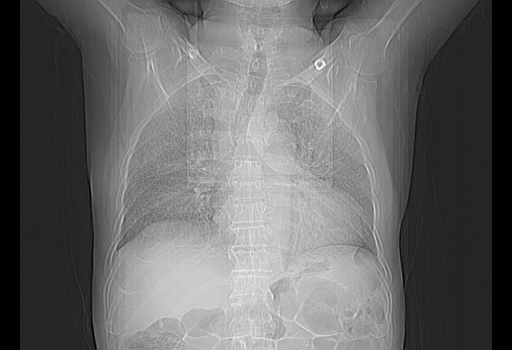

今天复查肺部CT,发现双肺广泛磨玻璃样改变。所以我把3月19日和5月9日相隔50天的肺部CT上传。请大家会诊。

2009年3月19日肺部CT片。

2009年3月19日肺部CT